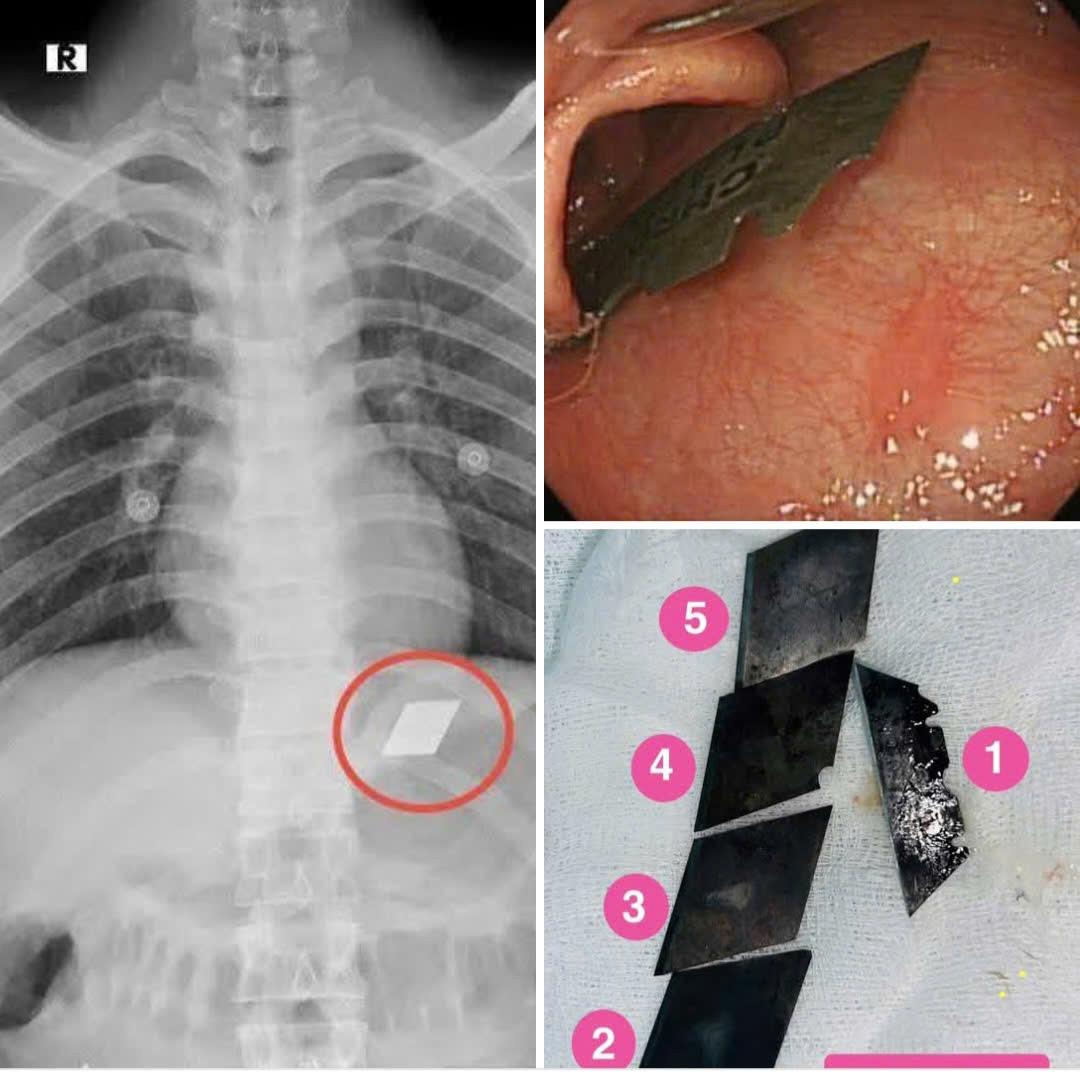

Ngày 21-7, Bác sĩ Lê Ngọc Long, Giám đốc Bệnh viện đa khoa Bình Dương (phường Thủ Dầu Một, TP HCM) cho biết ê kíp của Bệnh viên vừa thực hiện thành công ca phẫu thuật phức tạp.

Bệnh nhân là một người "ngáo đá", đã nuốt trọn bộ dao 5 món vào bụng.

5 mảnh dao được gắp ra khỏi bụng một nạn nhân "ngáo đá"

Bác sĩ Quốc Du, người trực tiếp thực hiện ca phẩu thuật đã lấy một nửa cây dao lam kẹt ở miệng thực quản, hạ họng và 4 mảnh dao rọc giấy trong dạ dày

Sau can thiệp nội soi gắp các mảnh dao ra ngoài, bệnh nhân được cho nhập viện theo dõi. Hiện tại đã ổn định và xuất viện.